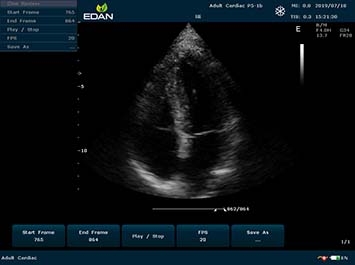

Качество визуализации:

- Тканевая гармоническая визуализация для высокой детализации

- Технология SCI для улучшенного контрастного разрешения

- Интеллектуальное подавление зернистости изображения

- Многолучевая технология с высокой частотой кадров

- Режим двойного отображения в реальном времени

B-режим, Двухмерное сканирование:

Да

Общая визуализация:

Да